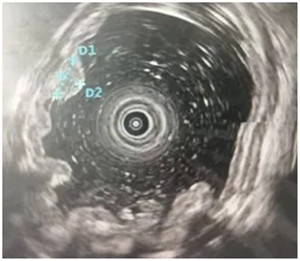

如果怀疑患者可能是类癌

我们需要先做个内镜下的超声内镜

协助诊断

明确后行ESD术